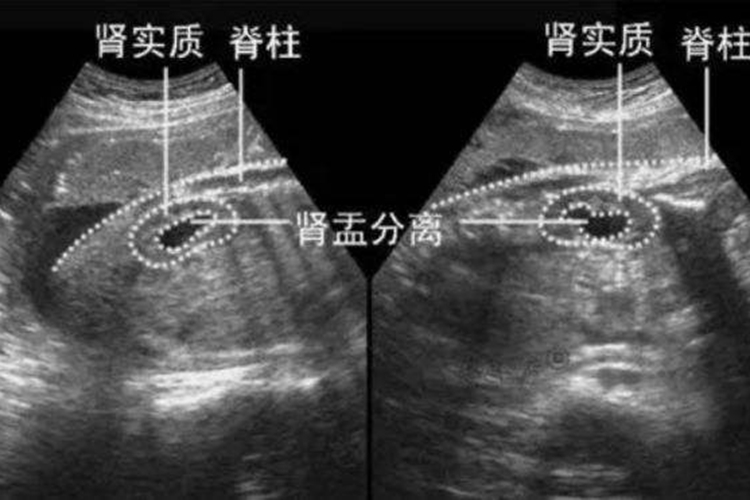

肾盂分离是肾积水的超声检查表现,可分为生理性肾盂分离与病理性肾盂分离。

生理性肾盂分离为肾盂内存有少量尿液,声像图出现肾盂回声分离,不同于尿路梗阻而引起的肾积水,在排尿后或利尿期过后,肾盂回声分离现象可消失。一般1.5cm以上的肾盂分离可确定为肾积水,而1.0cm以下的肾盂分离可能为生理性肾盂分离。

病理性肾盂分离声像图上高回声的肾窦内出现无回声区,肾窦分离扩张,分离大于1.5m,可能伴有肾盏扩张。扩张的肾盏间互相连接,肾皮质明显变薄,甚至菲薄呈线状。